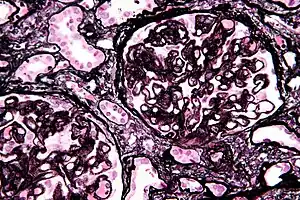

Micrograph of diffuse proliferative lupus nephritis showing increased mesangial matrix and mesangial hypercellularity. Kidney biopsy. PAS stain.

Lupus nephritis is an inflammation of the kidneys caused by systemic lupus erythematosus (SLE), an autoimmune disease.[3] It is a type of glomerulonephritis in which the glomeruli become inflamed. Since it is a result of SLE, this type of glomerulonephritis is said to be secondary, and has a different pattern and outcome from conditions with a primary cause originating in the kidney.[4][2] The diagnosis of lupus nephritis depends on blood tests, urinalysis, X-rays, ultrasound scans of the kidneys, and a kidney biopsy. On urinalysis, a nephritic picture is found and red blood cell casts, red blood cells and proteinuria is found.

Class II Mesangial proliferative glomerulonephritis 20% Mesangial hypercellularity and matrix expansion. Microscopic haematuria with or without proteinuria may be seen. Hypertension, nephrotic syndrome, and acute kidney injury are very rare at this stage.[9] Responds to high doses of corticosteroids